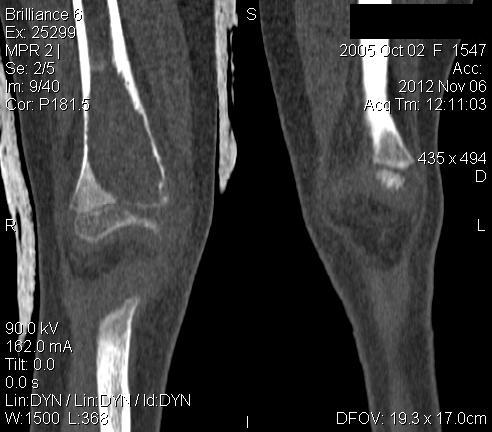

3 месяца назад в отделении была прооперирована девочка 7 лет с клинико- рентгенологической картиной аневризмальной кисты (открытая биопсия). Гистологическое заключение местных гистологов и ФНКЦ им. Д. Рогачева -аневризмальная киста. 2 недели назад девочка взята на костную пластику - на операции полный лизис костной ткани циркулярно на протяжении 10 см от эпифиза на 10 проксимальней и массивное артериовенозное крововтечение из оставшейся надкостницы . Операция закончена наложением стержневого аппарата и остановкой кровотечения тахокомбом, тампонадой мышцами. Повторная гистология неоднозначна. ФНКЦ им. Д. Рогачева дает прежний результат , ФГБУ РОНЦ НН Блохина -телеангиэктатическая остеосаркома, онкологи из института Герцена - киста .Как быть дальше. Кому верить и что делать? Заранее благодарен.

Судя по рентгенам и КТ, больше похоже на саркому, так как границы опухоли размыты. Аневризмальная киста обычно находится не по центру кости, а с одного края. Результаты гистологии надо всегда смотреть вместе с рентгенами. Если в каких-то из трёх центров видели только гистологию, то имеет смысл попросить их посмотреть и рентгены с КТ. Ежели всё видели и заключение не меняется, то можно попробовать послать в какой-нибудь очень крупный онкологический центр вроде Instituto Ortopedic Rizzoli в Италии или Mayo Clinic в США.